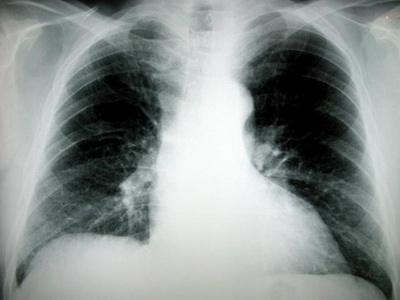

The chest X-rays, CT, cytological examination of sputum for sputum examination and treatment is Biopsy. Medical India becoming accessible due to the cybernetic revolution we can do immediately.